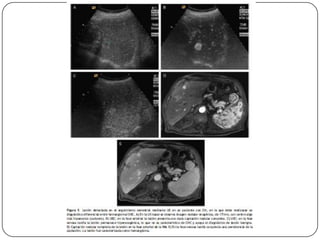

Auxiliares de diagnóstico

 RM

 No utiliza contraste intravenoso

 Es más eficaz que la TC para diferenciar el CH de

nódulos de regeneración

 TAC

 Sensibilidad del 68% con especificidad de 93%, se

utiliza para precisar las alteraciones vistas en el

usg.

Angiografía por resonancia

magnética

 Información sobre la anatomía arterial es útil para

excluir a algunos pacientes de ser tomados en

cuenta para la resección.

 La presencia de un tumor trombi en las venas

hepáticas, vena cava inferior o la vena portal,

pude alterar de forma significativa el enfoque de

tratamiento.

 Las exploraciones dinámicas de TC y de IRM

pueden documentar la relación del tumor con las

venas portales y hepáticas (y, en ocasiones, la

complicación de estas estructuras), delineando

los tumores para los cuales las posibilidades de

Karl RC, Morse SS, Halpert RD, et al.: Preoperative evaluation of patients for liver

curación quirúrgica son remotas.

resection. Appropriate CT imaging. Ann Surg 217 (3): 226-32, 1993